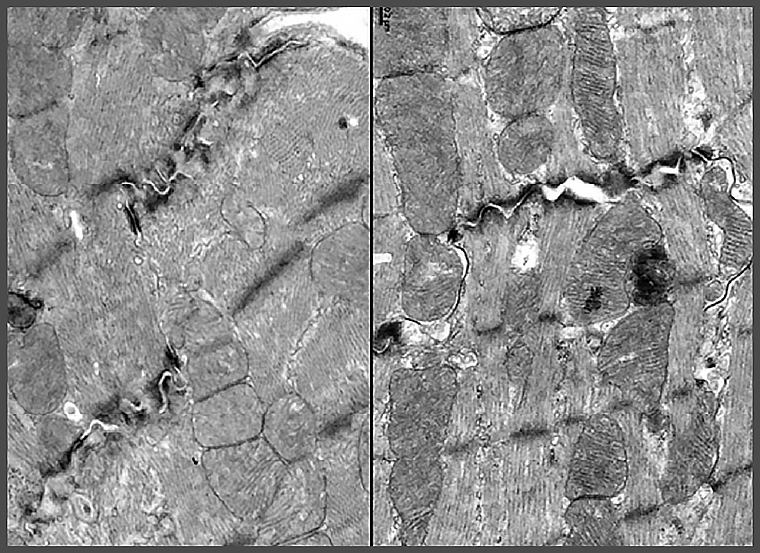

研究團隊發現,小紅莓會抑制心肌細胞中長壽基因CISD2的表現,使粒線體與鈣離子調控失衡,導致心臟收縮與節律出現問題。相反地,橙皮素可以重新啟動長壽基因CISD2,減少心肌細胞受損。

令人振奮的是,橙皮素不僅能撐起心臟保護傘,在動物實驗中,小紅莓處理的長腫瘤小鼠,注射橙皮素後,不僅顯著改善心臟功能,腫瘤體積也明顯縮小,顯示橙皮素不會影響小紅莓的抗癌力。橙皮素對心肌細胞的保護作用,研究團隊也運用由美國史丹福大學所提供的人類誘導性多能幹細胞(iPSC)衍生的心肌細胞加以驗證,強化支持橙皮素臨床應用的潛力。